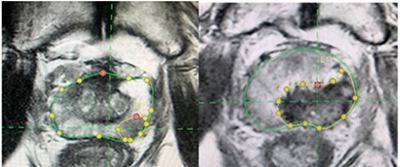

研究人员在该项Ⅱ期试验(PFLT-PC)中招募了100例前列腺特异性抗原(PSA)水平<15 ng/mL的、<T2c期的、国际泌尿病理学会(ISUP)分级分组为2~3的、多参数MRI有可见病灶的、局限性前列腺癌男性患者,在日间病房全身麻醉下给予ProFocal前列腺组织消融激光疗法的冷激光聚焦治疗(Medlogical Innovations)。

主要终点包括72小时内多参数MRI组织消融的充分性,以及治疗后3个月的活检情况。

结果显示,患者的中位年龄为66岁(IQR:60~72岁),中位PSA水平为5.9 ng/mL(IQR:3.9~7.6 ng/mL),中位前列腺体积为39 mL(IQR:30~51 mL),中位MRI病灶体积为0.84 mL(IQR:0.57~1.2 mL),中位治疗时间为60 min(IQR:47~70 min)。

在3个月的治疗区活检中,84%的患者未发现ISUP分级分组>2的前列腺癌。功能性结局显示,SHIM量表和EPIC量表性功能项目评分平均下降15%,其中12%的男性报告有勃起功能障碍。泌尿功能受到的影响极小,EPIC量表泌尿功能项目评分仅下降4.5%,其他功能指标评分无下降。